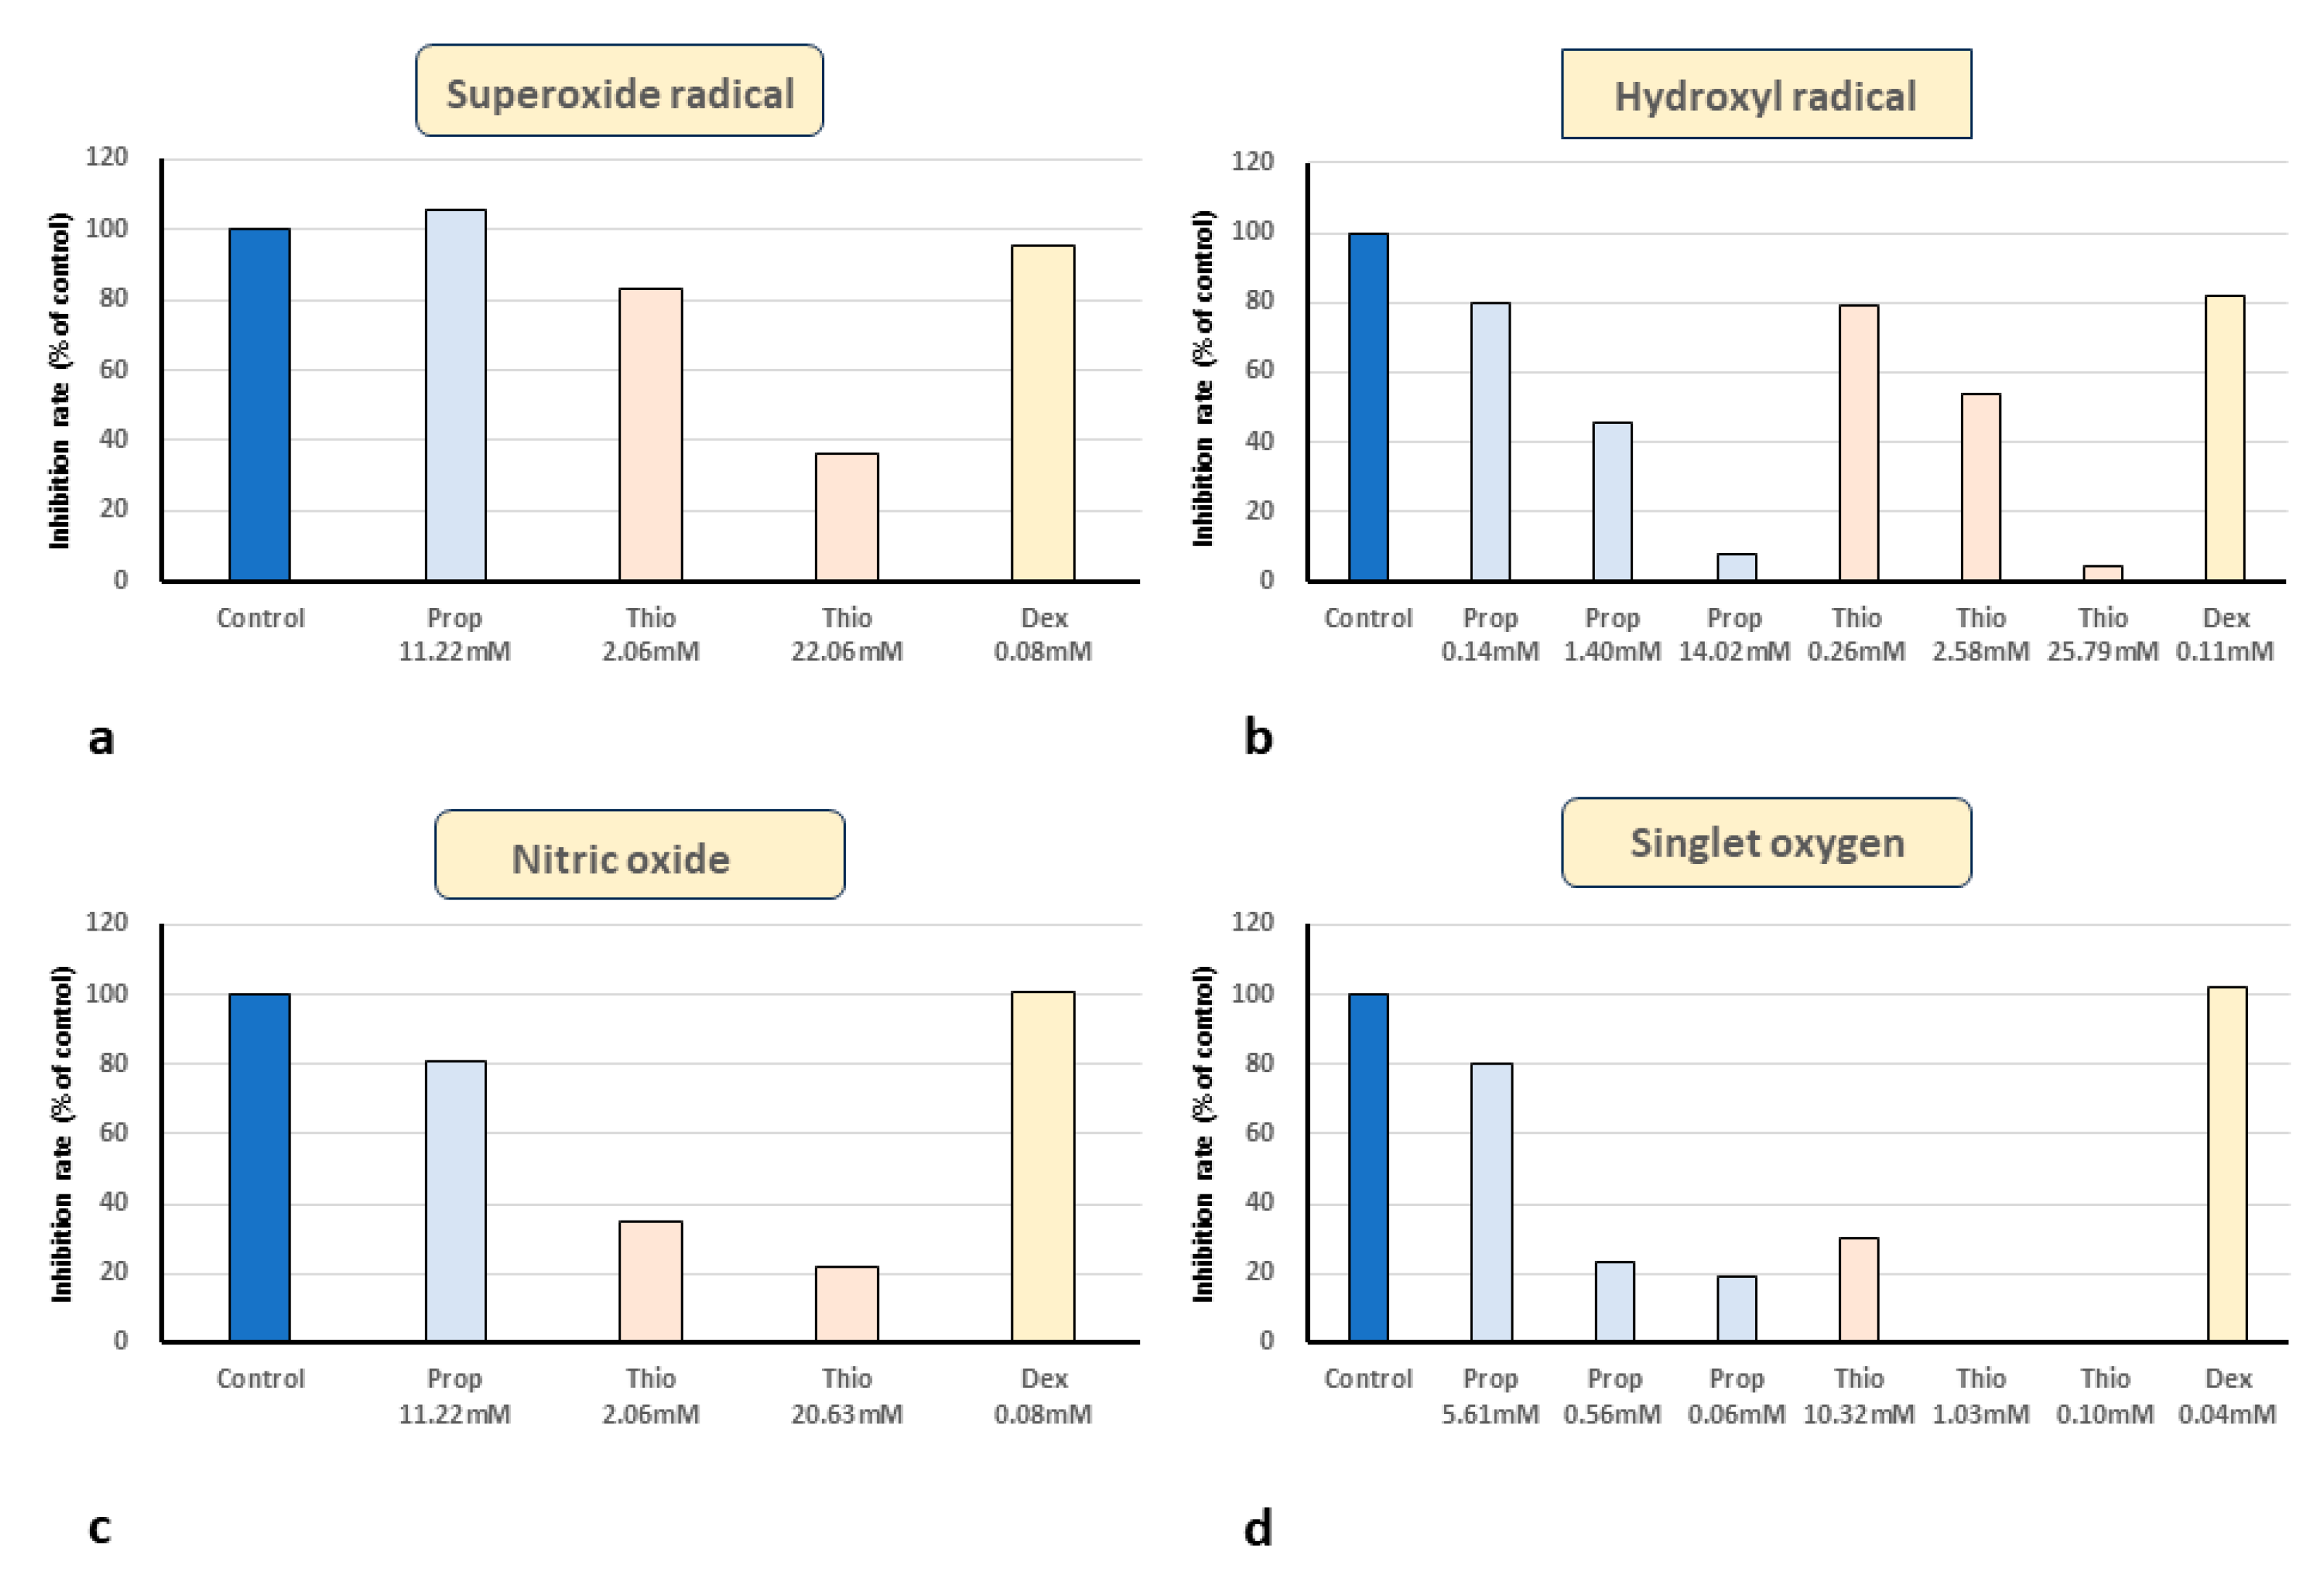

2.2. In Vitro ESR Method

3. Results